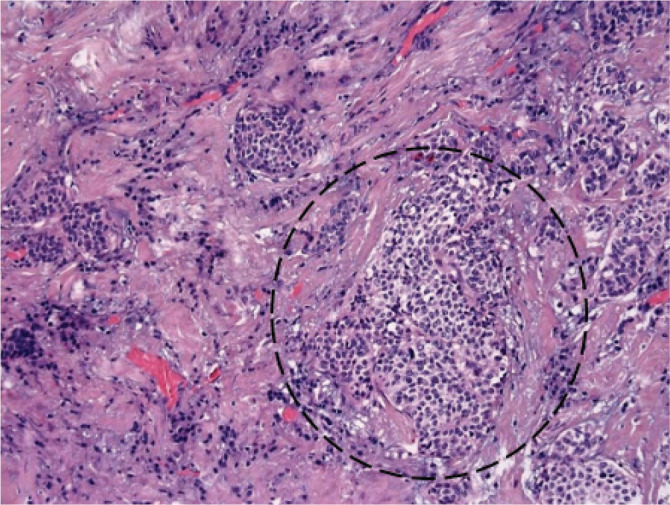

Because of the elevated tumor marker levels and the presence of a small adrenergic receptor-rich area detected with MIBG scintigraphy, the persistence of cancer was suspected. Thyroid US was performed several times to evaluate the lymph nodes. The cervical lymph nodes appeared smaller than 1 cm at the level VI on the left side, without visible metastatic changes. The small adrenergic receptor-rich area, which was visualized on MIBG scintigraphy, revealed normal thyroid tissue, possibly from the pyramidal lobe. Pyramidal lobe removal and unilateral central compartment lymph node dissection were considered because the initial tumor was detected in the middle portion of the left thyroid lobe. In 2 out of 5 dissected lymph nodes (up to 0.8 cm), tumor cells with “salt-and-pepper” chromatin (Fig. 6) and amyloid deposits (Fig. 7) were found. These findings confirmed the typical changes of MTC and the spread of the disease. The tissue of the pyramidal lobe was without pathological changes.

Figure 6.

Lymph node. Tumor cells with “salt-and-pepper” chromatin.